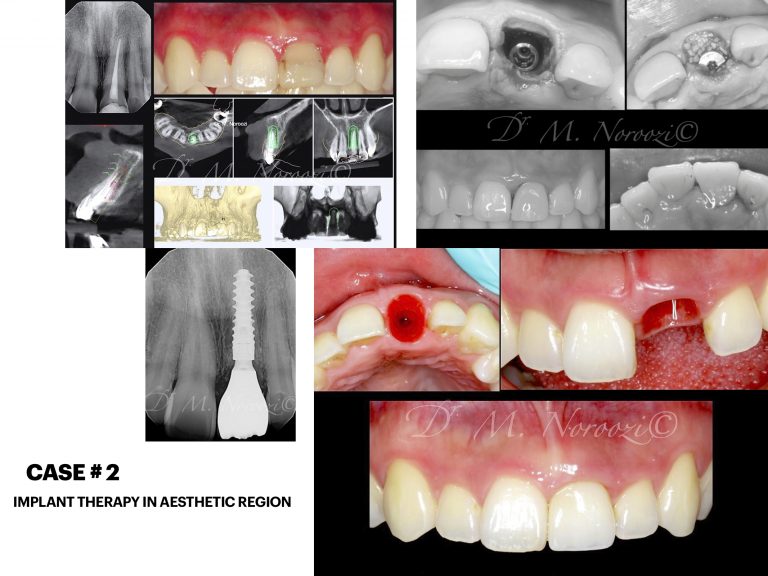

Before & Afters of Dental Implant Patients

Complete Dental Implant Cases Gallery

Surgical advances with SAME-DAY IMPLANTS in Vancouver BC

Using the most recent advances in dental implant technology, Dr. Noroozi is able to place single stage implants. These implants do not require a second procedure to uncover them but may require a minimum of six weeks of healing time before artificial teeth are placed. There are even situations where the implant can be placed at the same time as the tooth extraction and the artificial tooth can be inserted immediately following the implant placement – further minimizing your number of surgical procedures.

General Disclaimer: The results in the photographs are examples only and do not imply any certainty of the result of a procedure, and all outcomes are subject to the circumstances of the individual patient.